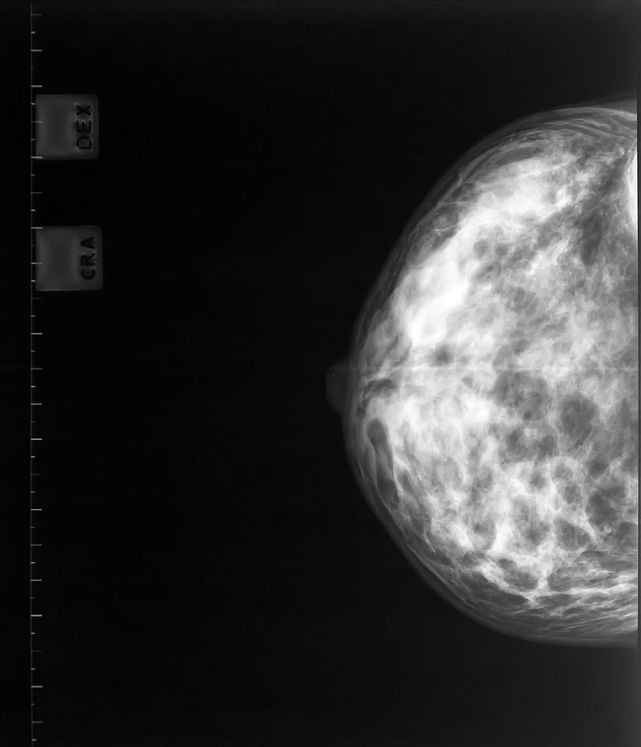

The latest study, which is published in the Journal of the Royal Society of Medicine, analyses mortality statistics recorded before and after 1988, the year that the National Health Service Breast Screening Programme began in the UK.

The results show that there has been no greater fall in deaths among women who underwent breast screening compared with those that didn’t.

Figures from the New Zealand Ministry of Health show that breast cancer mortality per 100,000 women dropped from 25.2 in 1999 to 19.9 in 2009. The publicly funded screening programme was introduced in New Zealand in 1998.